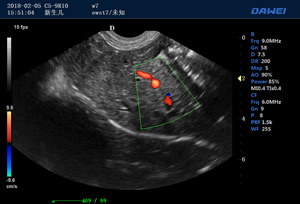

·支持B、C、PW、CW、寬景成像